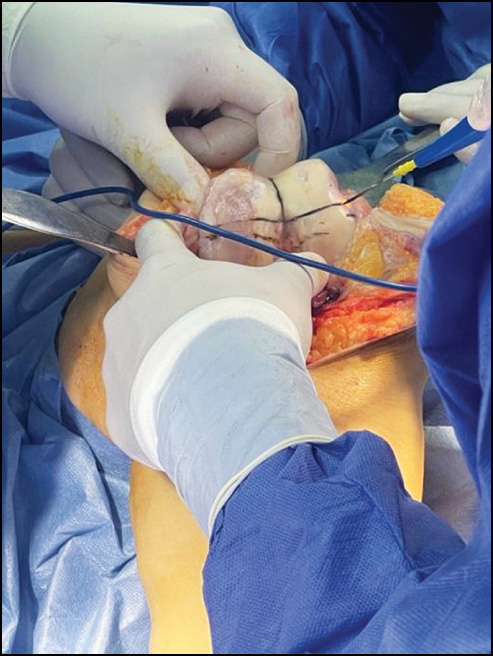

CASE 4. PATIENT 25

Age: 65 years.

Sex: Male.

Diagnosis: Bilateral advanced knee osteoarthritis.

Procedure: Bilateral simultaneous knee arthroplasty.

Associated illnesses: No associated comorbidities.

Postoperative follow-up: No postoperative complications were encountered.

Length of hospital stay: 6 days.

Radiological assessment (Fig. 23–26)

Fig. 23. Ap preoperative x-ray showing bilateral knee osteoarthritis.

Рис. 23. Предоперационная рентгенограмма с двусторонним остеоартритом коленного сустава.

Fig. 24. Lateral preoperative x-ray right and left knees showing osteoarthritis.

Рис. 24. Предоперационная боковая рентгенограмма правого и левого колена с признаками остеоартрита.